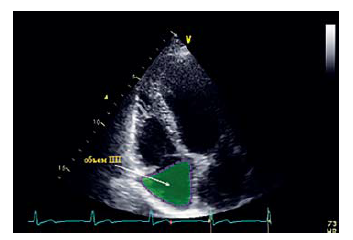

В международных рекомендациях 2010 г. к патологическим увеличениям относили абсолютные размеры и площадь правого предсердия (ПП) больше 18 см2. Затем с 2015 г. к увеличениям для ПП использовали индексированные продольный и поперечный размеры ПП и индекс объема для ПП. В соответствии с последними данными (EACVI, 2017) индекс объема для ПП должен составлять <30 мл/м2 у мужчин и <28 мл/м2 у женщин (рис. 4).

Рис. 4. Измерение объема ПП в «сфокусированном сечении на правых камерах»